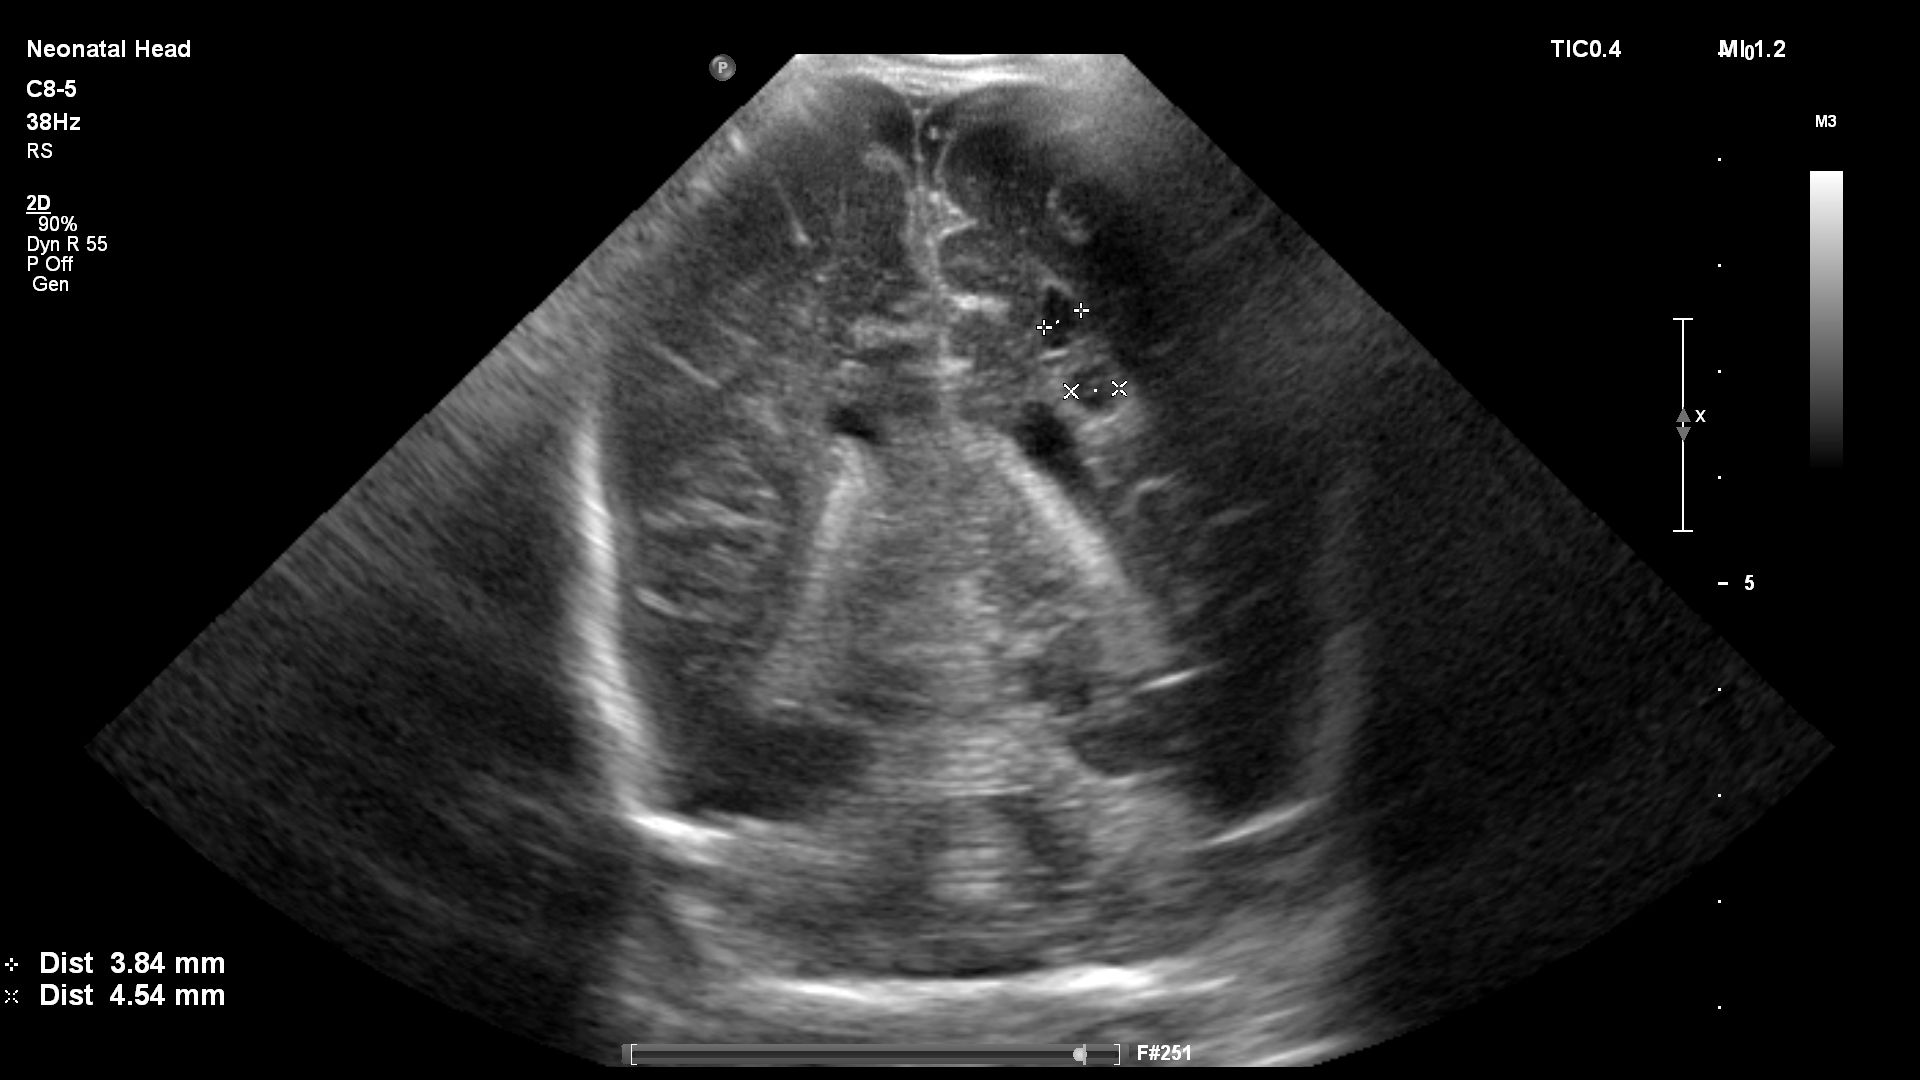

Preterm premature rupture of membranes (pPROM) before 22–24 weeks of gestation is considered previable and poses a high risk to the chances of successful delivery. Multicystic dysplastic kidney (MCDK) is the most common form of dysplasia of this organ, usually affecting 1 kidney. A prenatal suspicion of MCDK requires escalation of the clinical process to a reference center qualified and equipped for further diagnosis and treatment. We present a unique case of prenatal pPROM at 19 weeks of gestation in a pregnancy complicated by fetal MCDK as an interesting obstetric and neonatal patient story. We have not found any published evidence on the impact of coexisting fetal congenital malformations on a pregnancy affected by previable pPROM.

Agut T, Alarcon A, Cabañas F, Bartocci M, Martinez-Biarge M, Horsch S, et al. Preterm white matter injury: ultrasound diagnosis and classification. Pediatr Res 2020;87(Suppl 1):37-49.